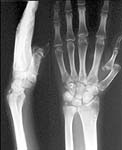

A male 25 y.o. was injured in boiler explosion Apr 2, 2002 and today admitted to our unit.

Except cominuted femoral fracture he has a neglected dislocation of left thumb. What management protocol would be optimal for the pattern? Leave as is? Acute open reduction? Gradual distraction by XF, with closed or open reduction? Then XF with hinges to start ROM?

This is a palmar dislocation. The main impediments to reduction would be the dorsal structures - EPB, EPL, APL. (Patel M, Dave J. Dislocations of the metacarpophalangeal joint of the thumb. Jr Hand Surg. (Br & Eur) 22-B; 4: 499-504) The sesamoids are seen close to the proximal phalanx, which suggests that the volar plate is intact apart from being pulled off the weak accordian attachment to the metacarpal head. I would suggest a lateral approach which would allow you to go both dorsal and palmar. Reduction, debridement of the arthrofibrosis and pinning (will give a stiff but stable MCP. One might be tempted to try dynamic ex-fix with early mobilisation to get some mobility.